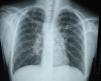

La radiografía de tórax inicial mostró infiltrado micronodular y reticular difuso con adenopatías hiliares bilaterales (fig. 1).

Se inició tratamiento con prednisona 2mg/kg/día e hidroclorotiazida 1.2mg/kg/día, con lo cual se observó mejoría clínica de su estado general, con remisión de la hepatomegalia y la esplenomegalia, del eritema nodoso, así como de las adenopatías y de la masa testicular. Posteriormente, desaparecieron las adenopatías mediastinales y los infiltrados pulmonares (fig. 10).

A su ingreso se detectó insuficiencia respiratoria crónica tipo I, sin repercusión cardiovascular, con hipoxemia, normocapnia e hiperlactatemia. La radiografía de tórax mostró infiltrado micronodular y reticular difuso con adenopatías hiliares bilaterales, concordante con el Estadio II de la clasificación de la American Thoracic Society para sarcoidosis torácica. Así mismo, la espirometría y la pletismografía reportaron una disminución de la relación VEF1/FVC, compatible con una neumopatía de patrón restrictivo leve como se ha descrito en las dos primeras etapas de la sarcoidosis pulmonar, que se normalizó después del tratamiento con prednisona.